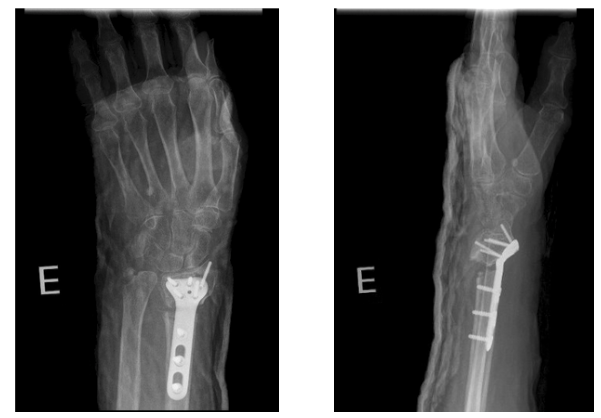

3-month follow-up